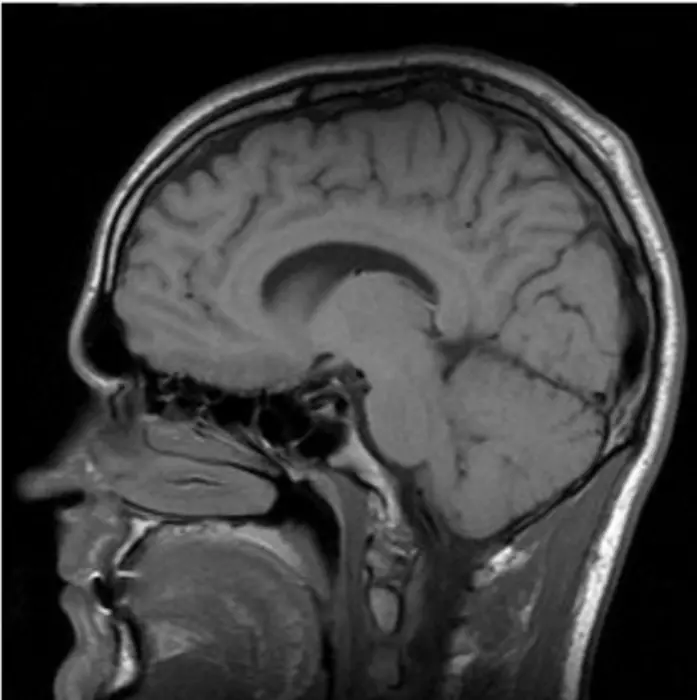

PD is known for its motor symptoms like slow movement, muscle stiffness, unstable posture, and abnormal walking. However, PD also includes non-motor symptoms such as cognitive issues, sleep problems, and mental health concerns. Traditionally, PD is associated with the degeneration of dopamine-producing neurons in a brain area called the substantia nigra. Recently, research has shown that PD also affects the cerebellum—a brain region mainly involved in coordinating movement.

Further, the review explored cerebellar imaging studies related to PD. Imaging studies, such as voxel-based morphometry, indicated a significant cerebellar reduction in patients with PD compared to healthy controls, implying neurodegeneration. Pathological analyses and postmortem examinations revealed neuronal damage in the cerebellum of patients with PD. Additionally, animal models of PD showed high levels of neuronal cell death and degeneration in the cerebellum. " While both animal and human studies have demonstrated pathological changes in the cerebellum of PD, further research is needed to explore its association with clinical symptoms ," adds Prof. Le.

Furthermore, the researchers noted that many resting-state functional magnetic resonance imaging studies identified altered functional connectivity between the cerebellum and other brain regions in patients with PD. They found that patients with PD also exhibited significant metabolic changes in various cerebellar subregions, correlating with motor symptoms, cognitive impairment, and psychiatric symptoms. Thus, the neuroimaging results highlighted cerebellar changes in PD that potentially serve as biomarkers essential for PD management.